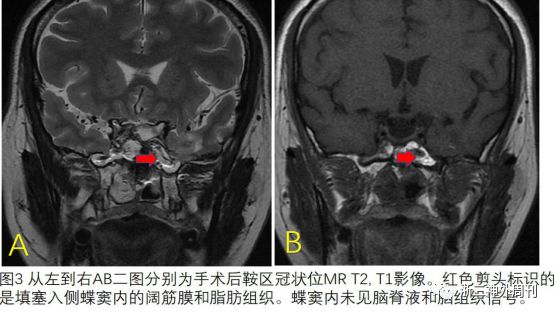

术后患者取平卧位,次日拔除鼻腔内膨胀海绵,持续腰大池引流4天,未见鼻腔部流液后拔除。术后患者恢复良好,1周后予出院。术后复查头颅MRI蝶窦内脑组织已清除,未见脑脊液积聚(图3)。